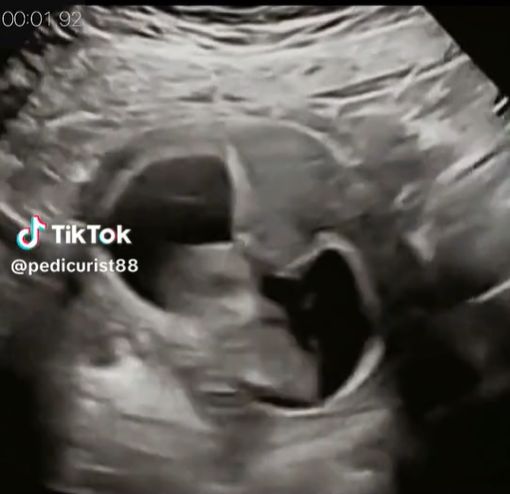

Mnóstwo polubień, komentarzy oraz udostępnień zebrało nagranie pochodzące z USG ciąży. Widać na nim 10-tygodniowy płód, który ma czkawkę. Dziecko rytmicznie podskakuje w brzuchu matki.

Badanie ultrasonograficzne uchwyciło moment, w którym płód ma czkawkęBadanie ultrasonograficzne uchwyciło moment, w którym płód ma czkawkę

Nagranie, które pojawiło się na TikToku, zostało opatrzone napisem, który informuje, iż czkawka u 10-tygodniowego płodu wystąpiła z powodu spożycia zbyt dużej ilości płynu owodniowego przez dziecko znajdujące się w łonie.

Widoczny na nagraniu płód rytmicznie podskakuje. Powodem jest czkawka

To prawda. Łapczywe połykanie płynu owodniowego, którym płód otoczony jest z każdej strony, skutkuje charakterystycznymi drganiami, które na obrazie USG wyglądają jak rytmiczne podskoki.